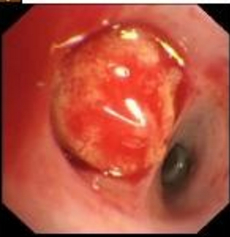

体温:38.0 ℃,脉搏:100次/min,呼吸:20次/ min,血压:130/87 mmHg(1 mmHg=0.133 kPa),身高:170 cm,体重:47.8 kg,BMI:16.53 kg/m2;双侧眼睑粘膜红肿,右侧鼻翼、鼻腔、左侧嘴角可见红色丘疹样溃疡形成(图 1A)。心、肺、腹部查体无明显异常。

A:在院治疗前期面部感染情况;B:出院时面部感染恢复情况 图 1 患者在院治疗前后面部皮肤感染表现